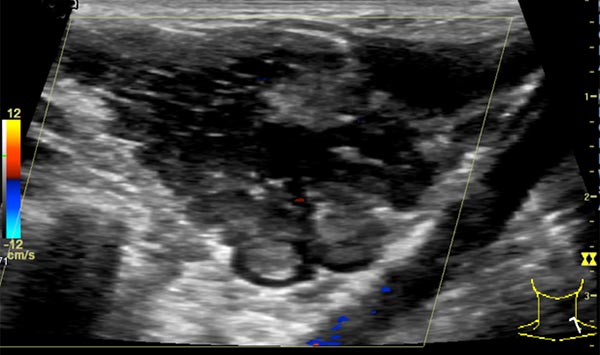

In der farbkodierten Duplexsonographie (FKDS) ist die venöse Malformation ebenfalls klar abgrenzbar. Da es sich um eine Slow-flow-Läsion handelt, zeigt sie hier praktisch keine Perfusion. Der Durchfluss durch die Läsion ist minimal. Farbsignale finden sich nur sehr wenige außerhalb der venösen Malformation, trotz niedrig gewählter Pulsrepetitionsfrequenz.